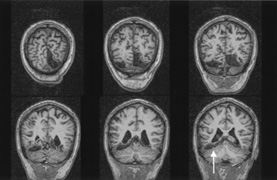

The upper and lower banks can also be involved separately. Ischemia can do this because the banks have separate blood supplies. Upper bank infarcts cause homonymous contralateral inferior quadrantanopia (Fig. 10) and lower bank infarcts cause superior quadrantanopia. Although altitudinal defects have been reported occasionally,47,48 most quadrantic defects do not align at the horizontal meridian, because the upper field merges without interruption into the lower field in the depths of the calcarine fissure. Thus it has been argued that quadrantic defects that respect the horizontal meridian are caused by involvement of area V2, surrounding striate cortex,49 which remains controversial. Quadrantanopias are three times more common with striate lesions than with optic radiation lesions.33 Striate quadrantanopias are more frequently isolated signs but can be associated with other signs of higher cortical visual dysfunction, such as pure alexia or hemiachromatopsia, whereas optic radiation quadrantanopias usually are accompanied by hemiparesis, dysphasia, or amnestic problems.33

Fig. 10. Striate quadrantanopia. A. A 68-year-old woman with a stroke 3 years previously, causing left inferior quadrantanopia. B. MRI shows infarct of the superior bank of the right calcarine cortex.